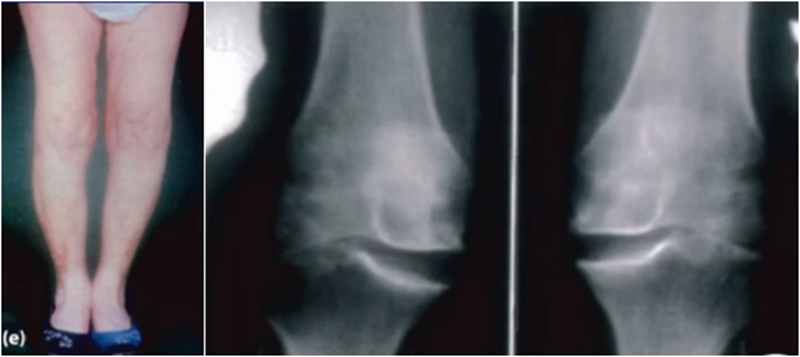

五、关于力线与假体位置——是否要求全长片?

牛津单髁课程表明,单髁只纠正关节内畸形,恢复下肢得病前的力线,不纠正关节外畸形。

但实际术后需要通过全长片来判断是否能取得好的力线,判断有无过度矫正或矫正不足的情况出现。还需要通过全长片区分内翻畸形的来源在哪里,是否能矫正,对适应证的选择有一定帮助。如果术后下肢整体力线外翻3°,则说明外侧间室压力明显升高。

小结:对于下肢整体力线,首先保证术后力线不能外翻,术后力线内翻不能超过10°,而术前关节外畸形不能超过10°。

除了下肢整体力线,还要考虑假体位置。理想状态下,假体位置对位好,力线轻度内翻。

牛津单髁在假体评判中,提到股骨内外翻有10°容忍度,胫骨内外翻有5°,股骨屈伸在0-15°之间,胫骨后倾在 7-(﹣5)后倾之间。但评判标准中没有提到此种方式是基于全长片还是局部片。

文献中建议假体内外翻不大于4°,如果假体出现外翻,后倾大,会造成内侧皮质压力异常增高,增加内髁骨折风险。如果假体内翻超过5°,增加胫骨平台松动风险。

但有时候力线好,假体和外侧关节线会成角,那么对于此种情况,应如何判断假体位置内外翻定义?和外侧关节线比较,属于外翻假体;和下肢机械轴比较,属于中立位假体。

小结:判断股骨胫骨假体位置,是基于局部X线的判断,是考虑行走时关节线的方向为基准,此时内外翻不能超过5°,而不能从全长片来判断。